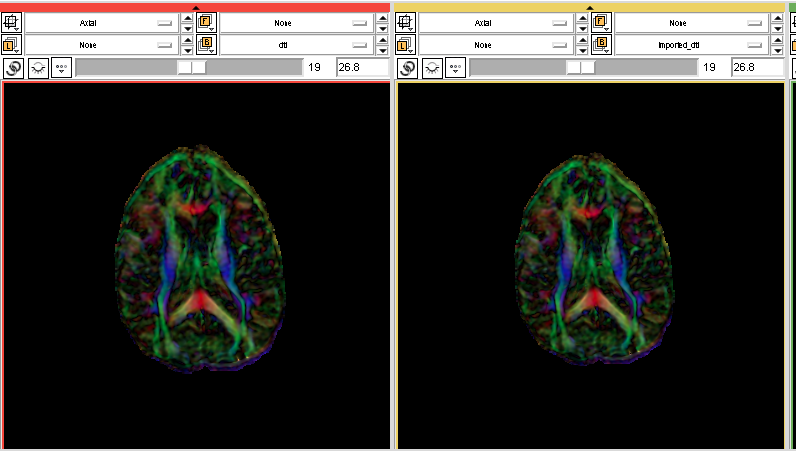

- Snapshots: (visualization of Nrrd files in Slicer, visualization of Nifti files in dti-tk)